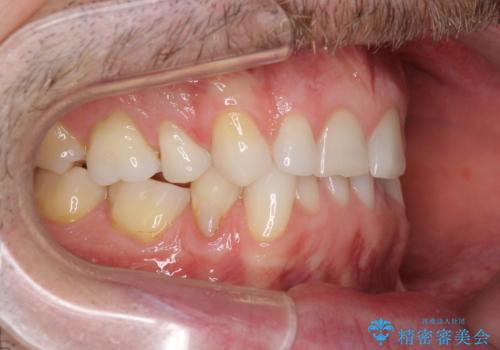

- 上下前歯の叢生を気にして来院された患者様です。

抜歯矯正をした後戻りということで、歯列不正はそれほど大きくなかったため、インビザライン・ライトを用いて矯正治療を行うこととしました。

前歯のデコボコが残っており、シミュレーション通りに動いていない部分がありましたが、再矯正であることやご本人の満足いくところまでデコボコが改善されたとのことで、治療を終了することとしました。